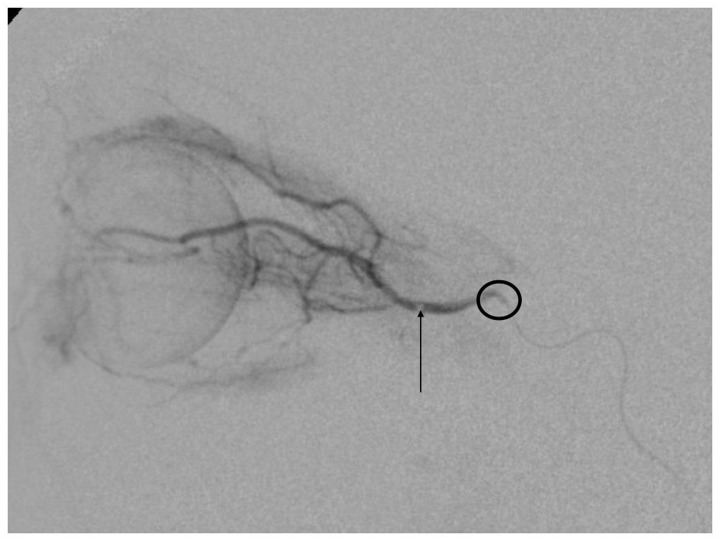

The most serious complication we had was a retinal hemorrhage that resolved after several weeks. It was the only case in which the microcatheter was navigated distal in the OA. The force exerted on the syringe for drug injection probably caused damage to the retina (Figure 4). An anaphylactic shock was caused by administration of carboplatin during the procedure; the patient responded well to medication without consequences. Some patients presented bradycardia and hypotension during the procedure; it is probably produced by a reflex triggered by navigation of the microcatheter in the cavernous segment of the ICA.8

Figure 4.

Digital subtraction angiogram (DSA). The arrow shows the tip of the microcatheter in the ophthalmic artery (OA), too distal to be safe for superselective ophthalmic artery chemotherapy. The circle surrounds the ostium of the OA.